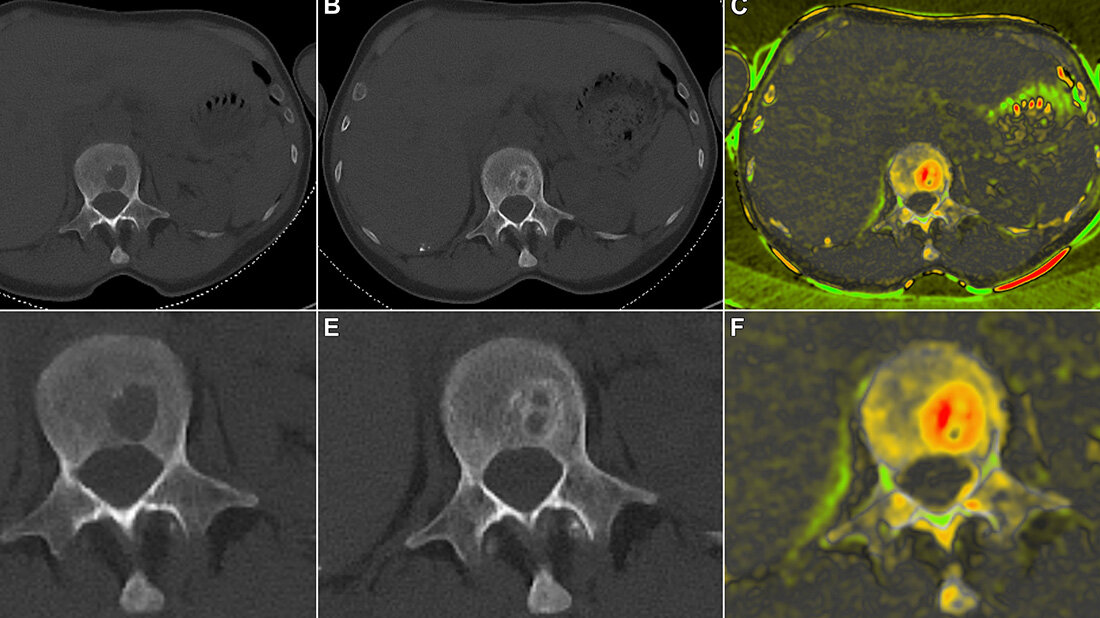

Am Uniklinikum Würzburg haben die Radiologen Dr. Jan Peter Grunz und Privatdozent Dr. Andreas Kunz unabhängig voneinander Röntgenbilder beurteilt, die von insgesamt 20 Patientinnen und Patienten mit einem neu diagnostizierten Multiplen Myelom vor und nach der standardisierten E-KRd-Therapie mittels Computertomografie erstellt wurden. „Die erste Herausforderung war das Finden und Messen der Läsionen zu beiden Zeitpunkten“, kommentiert Grunz, der die Ergebnisse als Erstautor im Fachjournal Cancers publiziert hat. Insgesamt sind den Radiologen 108 Läsionen aufgefallen, wovon 94 von beiden entdeckt wurden, 14 nur von jeweils einem. „Unterm Strich haben wir in der Studie gezeigt, dass wir die Läsionen mit einer Standardabweichung von 1,2 Millimetern verlässlich erfassen und messen können“, resümiert Grunz. Gemeinsam mit dem Bioinformatiker Dr. Dirk Hasenclever aus Leipzig haben die Radiologen aber nicht nur ein quantifizierbares Maß geliefert, welches man auf andere Studien übertragen kann, sondern auch den Remineralisierungsprozess qualitativ dargestellt. „Mit einer speziellen Farbkodierung konnten wir die Regeneration im inneren und äußeren Bereich der Knochen sichtbar machen“, erläutert Jan-Peter Grunz.